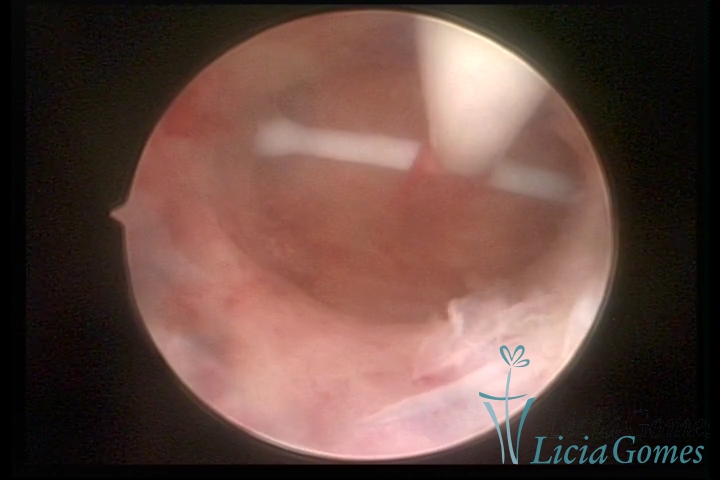

Uterine cavity with IUD

×